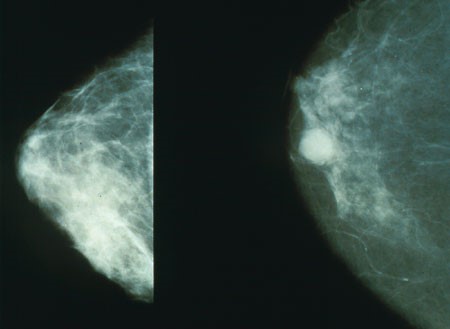

ממוגרפיה של שד נגוע בסרטן (מימין) ובריא (משמאל) | צילום: מכון הבריאות הלאומי, ארה"ב

במקרה של סרטן השד הוכח הקשר של 10-5 אחוזים מכל מקרי המחלה לנוכחותם של גנים "סרטניים" שעוברים בתורשה מההורים לצאצאים. הגנים האלה הם גנים שעברו מוטציות, כלומר טעויות "קידוד" שנכנסו לצופן הגנטי ושינו אותו. חלק מהטעויות הללו חסרות כל משמעות, אבל לאחרות עלולה להיות השפעה גדולה על הפוטנציאל שלנו לפתח מחלה תורשתית או תסמונת לא רצויה.

מחקר משותף של בית החולים קולג' לנשים בקנדה ובית הספר לרפואה פומראניאן בפולין גילה לאחרונה שמוטציות בגן בשם RECQL מעלות את הסיכוי לחלות בסרטן השד. החוקרים חקרו את פרופיל הגנים של נשים בעלות היסטוריה משפחתית של סרטן השד והשוו אותו לנשים שלא חלו בסרטן ושאין להן היסטוריה משפחתית של המחלה. אצל הנבדקות הפולניות מצאו החוקרים מוטציה בגן RECQL שנוכחותה מעלה פי חמישה את הסיכוי לחלות בסרטן השד בהשוואה לנשים ללא המוטציה.

במקביל גילתה קבוצת החוקרים הקנדית שאצל נשים קנדיות-צרפתיות בעלות רקע תורשתי למחלה קיימת מוטציה אחרת באותו גן, שמופיעה אצלן בשכיחות גבוהה פי 50 ביחס לקבוצת הביקורת. ככלל, החוקרים גילו שהמוטציות בגן הזה נדירות למדי, אך לנשים שנושאות אותן יש סבירות של 50 אחוז לחלות בסרטן השד.